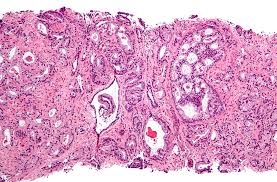

- 전립선 생검 (biopsy)